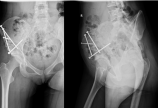

病人,女性,89岁,主诉:摔伤后左肩关节疼痛,活动受限3小时,同时患者有较严重的心血管疾病。病例相关资料见下图      考虑到肩关节脱位可能损伤到神经,因此值班医生连夜在手术室麻醉下手法复位至半脱位状态,但半脱位状态无法解决,那为什么复不上?下一步怎么办?1.再次闭合手法复位?2.切开直视下复位修复骨折?3.切开,软组织松解复位?4.切开,行关节盂骨折复位内固定?5.其他治疗? 请思考!见下图       此时,面对这样的病例,作为骨科医生,一定要进行详细检查(包括影像学资料)。现在让我们来重新审视这个病例!      关节镜下复位固定